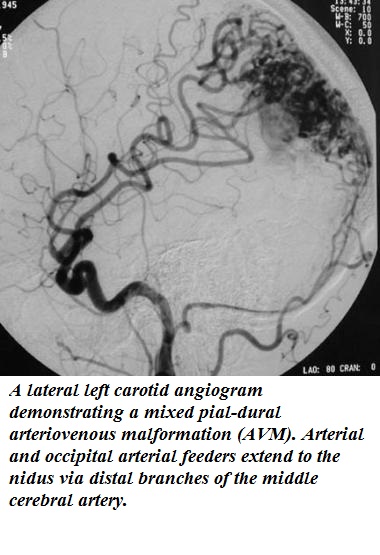

Сосудистая мальформация кожи лечение обследование - фото презентация